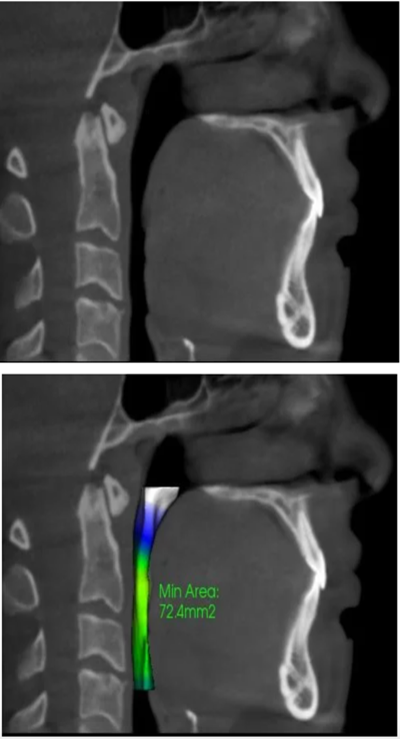

These are examples of normal and restricted airway volumes due to airway obstruction: